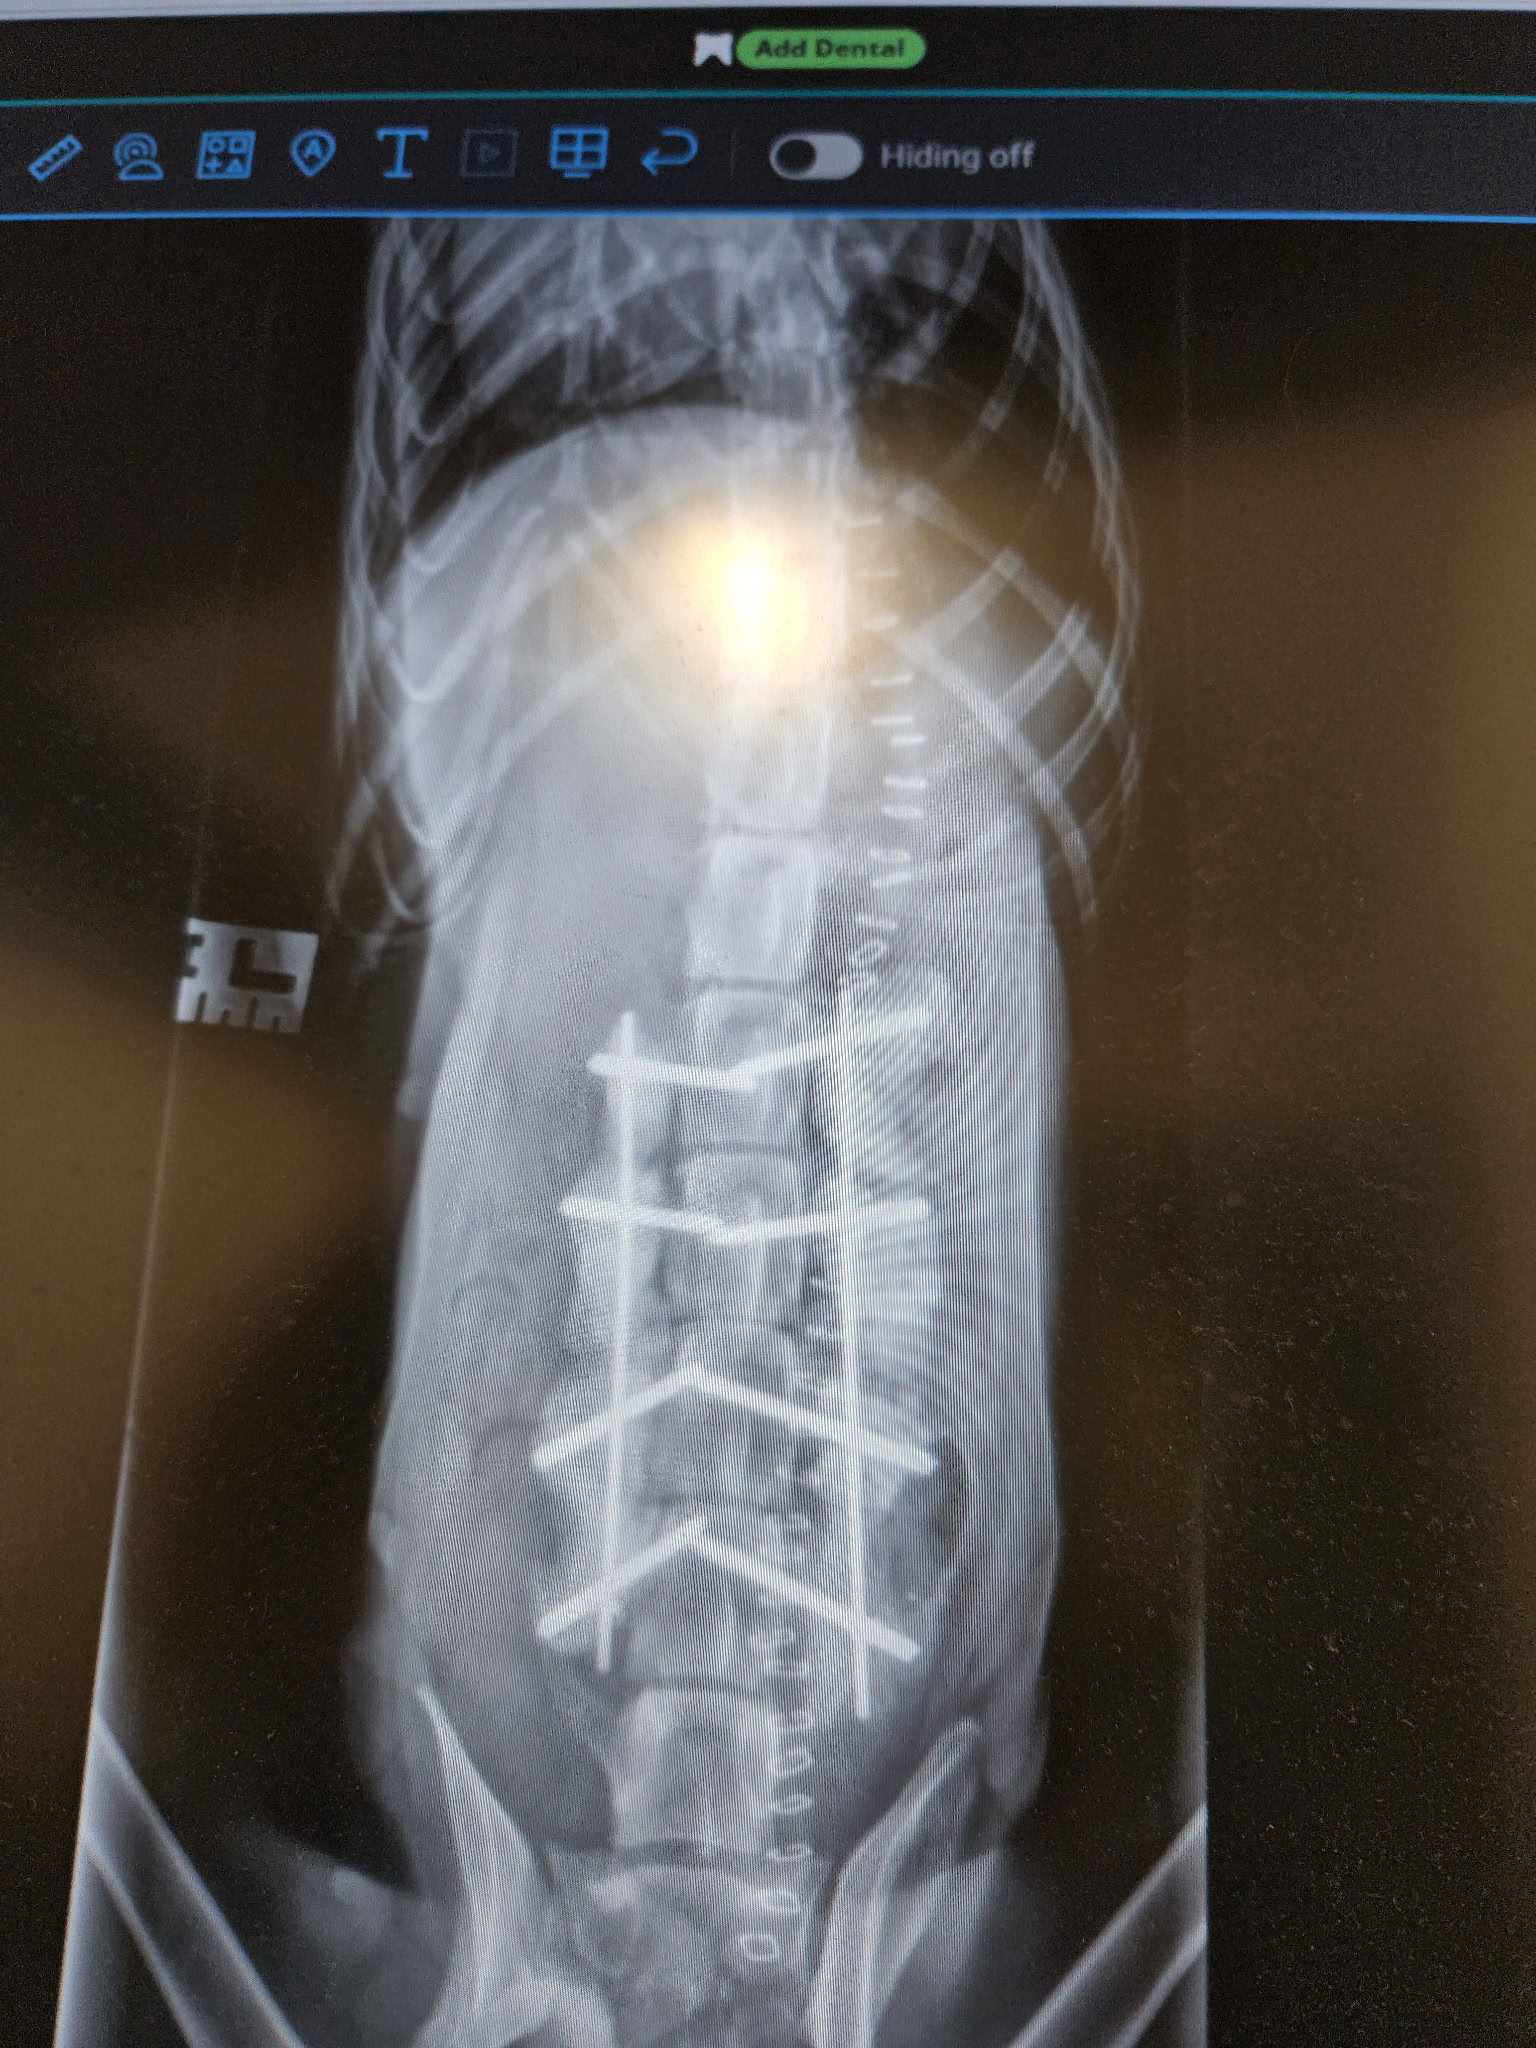

One notable beneficiary of Dr. Vetter’s donation this holiday season is Noel, a dog that was hit by a car and required urgent back surgery. Thanks to the Goochland Pet Lovers, Noel's surgery was successfully performed at Partner Veterinary Clinic. She is now recovering in a veterinary rehabilitation clinic, funded partially by Dr. Vetter’s donation.

Noel xray 2Noel xrayNoel 1Noel 2Noel 3 Dr. Erica Ditzler and NoelNoel 5Noel 6 Noel at Partner Veterinary